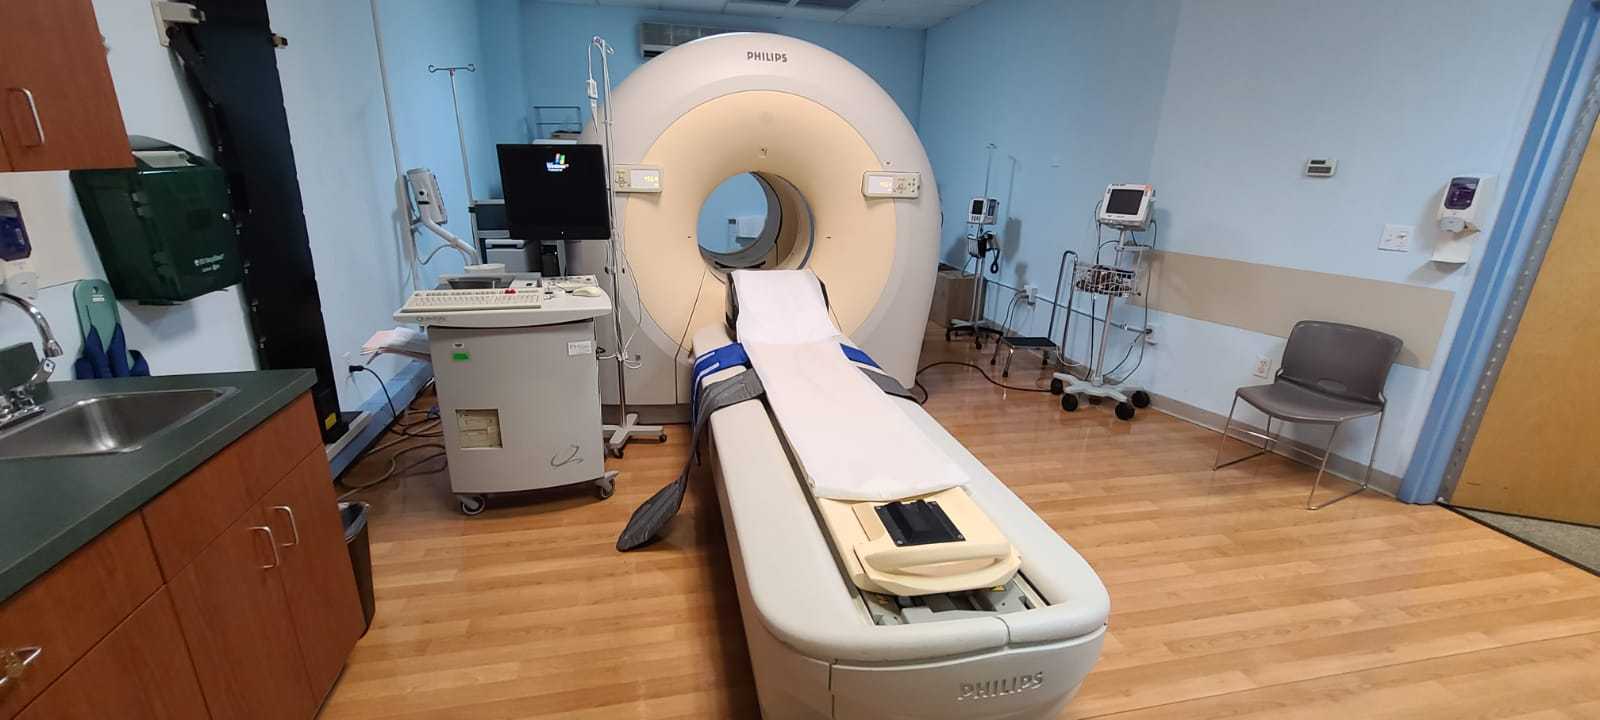

Moses Campus, along with Children’s Hospital at Montefiore Einstein, features 726 adult inpatient beds and 106 pediatric inpatient beds. The facility also offers services to outpatients. As an NCI-Designated Cancer Center, Moses provides diagnostic and therapeutic modalities through an active theranostics program. While training at Moses, residents partake in a particularly rigorous program in oncologic and non-oncologic pediatric and adult nuclear medicine. Our Transplant Center, also on-site, affords residents the ability to evaluate organ physiology pre- and post-transplant.

Our 431-bed Jack D. Weiler Hospital is located adjacent to the Albert Einstein College of Medicine in the Morris Park section of the Bronx. While at Weiler, residents participate in independent, hands-on training, with a particular focus on emergency cases and nuclear cardiology studies overseen by an attending. Residents are also exposed to much of their on-call experience at this location.